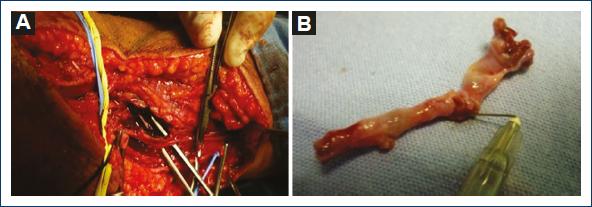

Patient with a case of gunshot wound to the right arm that occurred 1 month before. Since then, he reported paraesthesia in the fingers of his right hand and a drop in temperature. He was assessed at a family medicine unit in a community in Oaxaca and sent to a hospital in Mexico City. The patient was seen at the outpatient clinic of the hospital, where he was referred to the orthopedic service for a suspected fracture of the arm. On reviewing the orthopedic films, the patient was referred to the angiology service, which, on physical examination, observed gunshot wounds in the upper third of the external lateral face of the right forearm, healed as an entrance wound with an exit wound in the lower third of the internal lateral face of the arm with a healed wound. It also revealed increased volume in the elbow with ecchymosis, absence of radial and ulnar pulses, hand pallor, and distal hypothermia (Fig. 1). Doppler and duplex ultrasound was performed, where a total section of the humeral artery with collateral flow was reported. The patient was admitted for arteriography, which reported a lesion of the right humeral artery with flow through collateral circulation, permeable ulnar and interosseous arteries, and absence of flow of the radial artery (Fig. 2). A vascular exploration was scheduled for an inverted S incision on the humeral artery with extension to the forearm, locating extensive hematoma infiltrated in muscle tissue, humeral artery with irregularities in its wall, secondary to firearm burns, 50% laceration of the arterial wall with intra luminal hematoma without palpable flow (Fig. 3). After verifying good proximal humeral flow by thrombectomy with Fogarty catheter 4 and distal with Fogarty catheter 3 with excellent reflux of the distal humeral artery, a reversed saphenous vein graft was placed. Once the procedure was finished, the patient recovered proximal and distal pulses and was sent to the orthopedic unit to continue management of the bone lesion (Fig. 4). Post-operative management continued with unfractionated heparin with a timetable after discharge from the orthopedic unit and was managed with platelet antiaggregants for 3 months. Patient's evolution was satisfactory, medication was suspended, and he was discharged due to improvement.

Figure 2 A: arteriography of the humeral artery with occlusion and lesion of the intima with collateral circulation. B: fracture of the upper third of the right radius.